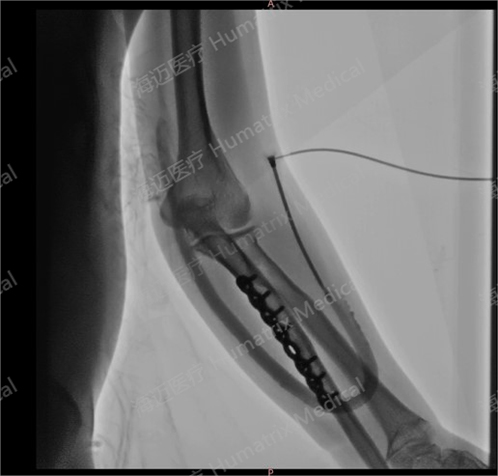

臨床試驗患者使用LineMatrix耐邁通?生物型人工血管長期血液透析,血管造影通暢。

臨床隨訪結(jié)果顯示,產(chǎn)品完成植入后,患者術(shù)后3月初級通暢率90.9%,累積通暢率100%;術(shù)后6月初級通暢率80.8%,累積通暢率100%。人工血管未引發(fā)人體免疫反應(yīng),無感染及動脈瘤等并發(fā)癥發(fā)生,產(chǎn)品性能明顯優(yōu)于ePTFE人工血管,臨床效果優(yōu)異。